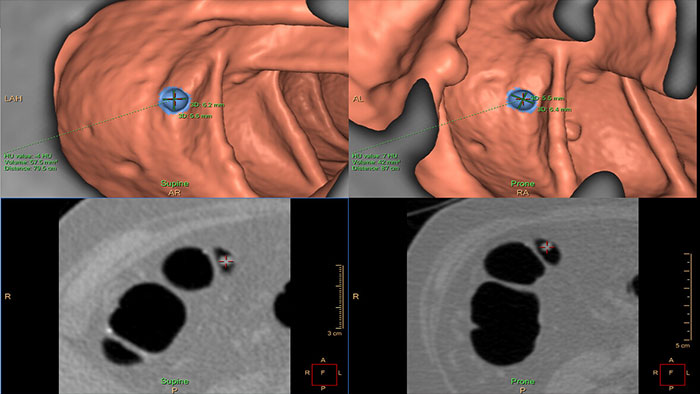

Automatically detect potential polyps in CT colonography exams

VC VeraLook CAD* uses image processing and pattern recognition technology identify colon polyps in CT colonography images, which can help streamline the reading process and improve workflow for radiologists while supporting accuracy, consistency and productivity in colon cancer screenings. Indicated for use as a second read, VeraLook is designed to enhance clinician accuracy and efficiency.

Reducing reading times in virtual colonoscopy

Enables 3D visualization of colon scans. The application automatically segments the air-filled colon and displays a calculated navigation path. The Perspective Filet view provides a synchronized display of the full colon surface wall with a single unidirectional view, reducing the need to review in both directions.